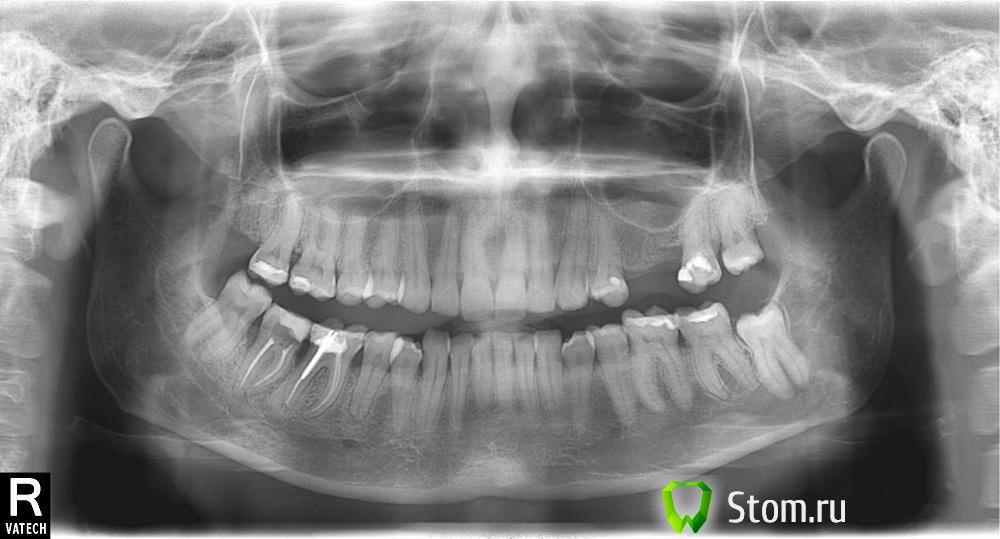

Tinka Опубликовано 20 апреля, 2012 Поделиться Опубликовано 20 апреля, 2012 День добрый! Будьте добры, в клинике сказали, что мне необходимо сделать открытый кюретаж внизу слева на 8,7,6-ку и сверху на 7,6-ку. Хотелось бы понимать, что меня не разводят, ввиду того, что снимок я читать не умею разумеется и очевидно ничего не беспокоит. Спасибо! Ссылка на комментарий

Джоэл Опубликовано 14 мая, 2012 Поделиться Опубликовано 14 мая, 2012 Здравствуйте, тут необходим конечно же осмотр с измерением глубины пародонтальных карманов.И одного ОПГ снимка для ответа на ваш вопрос мало. Снимок только показывает уровень кости. А для пародонтологической консультации этого мало. Если Вы сомневаетесь в докторе,то сходите на консультацию в ещё какую-нибудь клинику к врачу пародонтологу. И тогда возможно всё разъяснится. И ещё хочу Вам сказать, если идти к врачу с такими мыслями(меня разводят),то лучше сидеть дома! Ссылка на комментарий

Большой Зеленый Опубликовано 14 мая, 2012 Поделиться Опубликовано 14 мая, 2012 да действительно нужен кюретаж, даже по снимку видно Ссылка на комментарий